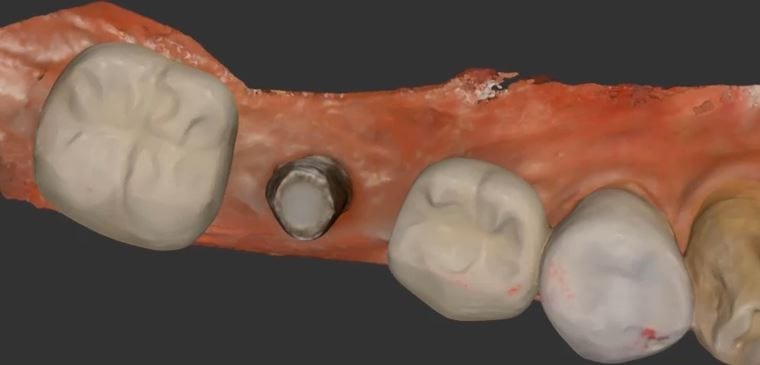

One of the biggest hassles in most software is to plan a guided surgery case when the tooth is still present in the arch. Some software will force you to […]